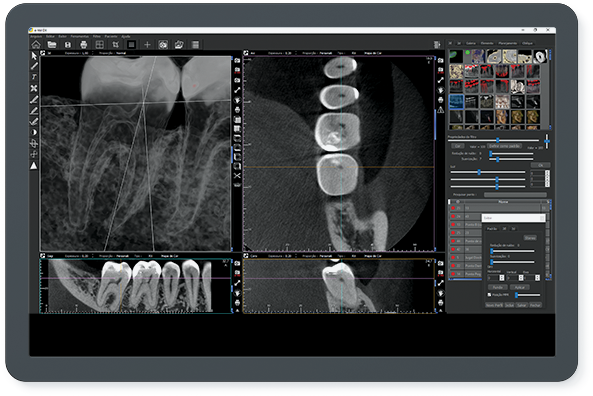

A empresa criou um sistema de radiologia odontológica que proporciona imagens realistas, oferecendo um nível de detalhamento profundo, permitindo a interpretação correta, eficaz e rápida do profissional. “O resultado final é surpreendente. Incrível. Já temos feedbacks extremamente positivos de profissionais renomados em todo mundo”, comenta do criador da empresa, Roney Rocha.

Entre os produtos oferecidos pela CDT Software é o E-VOL DX, reconhecido por pesquisas acadêmicas nacionais e internacionais de odontologia, possibilita imagens mais nítidas e com maior riqueza de detalhes! “O e-Vol DX é um software que supre demanda dos tradicionais aparelhos de radiologia. Compatível com os principais equipamentos do mercado, ele é composto por filtros e ferramentas que transformarão seus laudos”, ressalta.

Além disso, o e-Vol DX está em constante atualização para atender e antecipar-se às demandas dos profissionais da área de radiologia odontológica. Por isso, é um investimento seguro e eficaz e que não estará defasado. Com todos os recursos que garantem obter as melhores imagens de seu tomógrafo, o e-Vol DX possibilita otimizar o tempo de produção com o uso de ferramentas exclusivas.